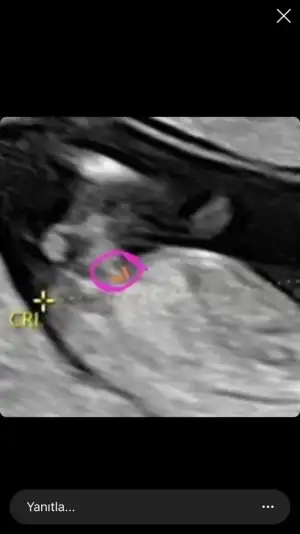

3 çizgi nasıl oluyor acaba 😂😂 bn hiç görmüyorum o çizgiyi 😂

Üç çizgi bu oluyor cnm çiziyor zaten kendisi o dakikadan sonra kız diye gittim doktoruma oda kız dedi zaten gösterdi☺️☺️☺️